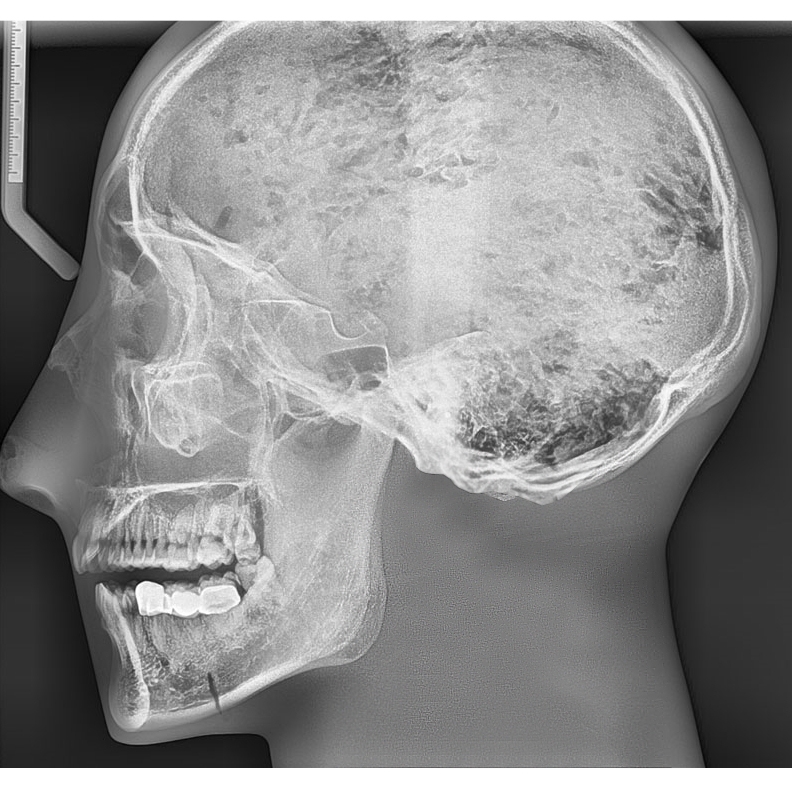

1. 模型包含具有天然齒列的真實人類頜骨和5-7截頸椎,整體包埋于軟組織等效材料中

2. 頭骨是醫(yī)學教學用頭骨,沒有降解跡象

3. 牙齒為未脫落的天然牙齒,部分牙齒有牙科修復痕跡。

4. 模式可顯示完整的頭部骨骼解剖結構,但是沒有軟組織或軟骨解剖,沒有氣管

頭骨與下頜骨及不含頸椎